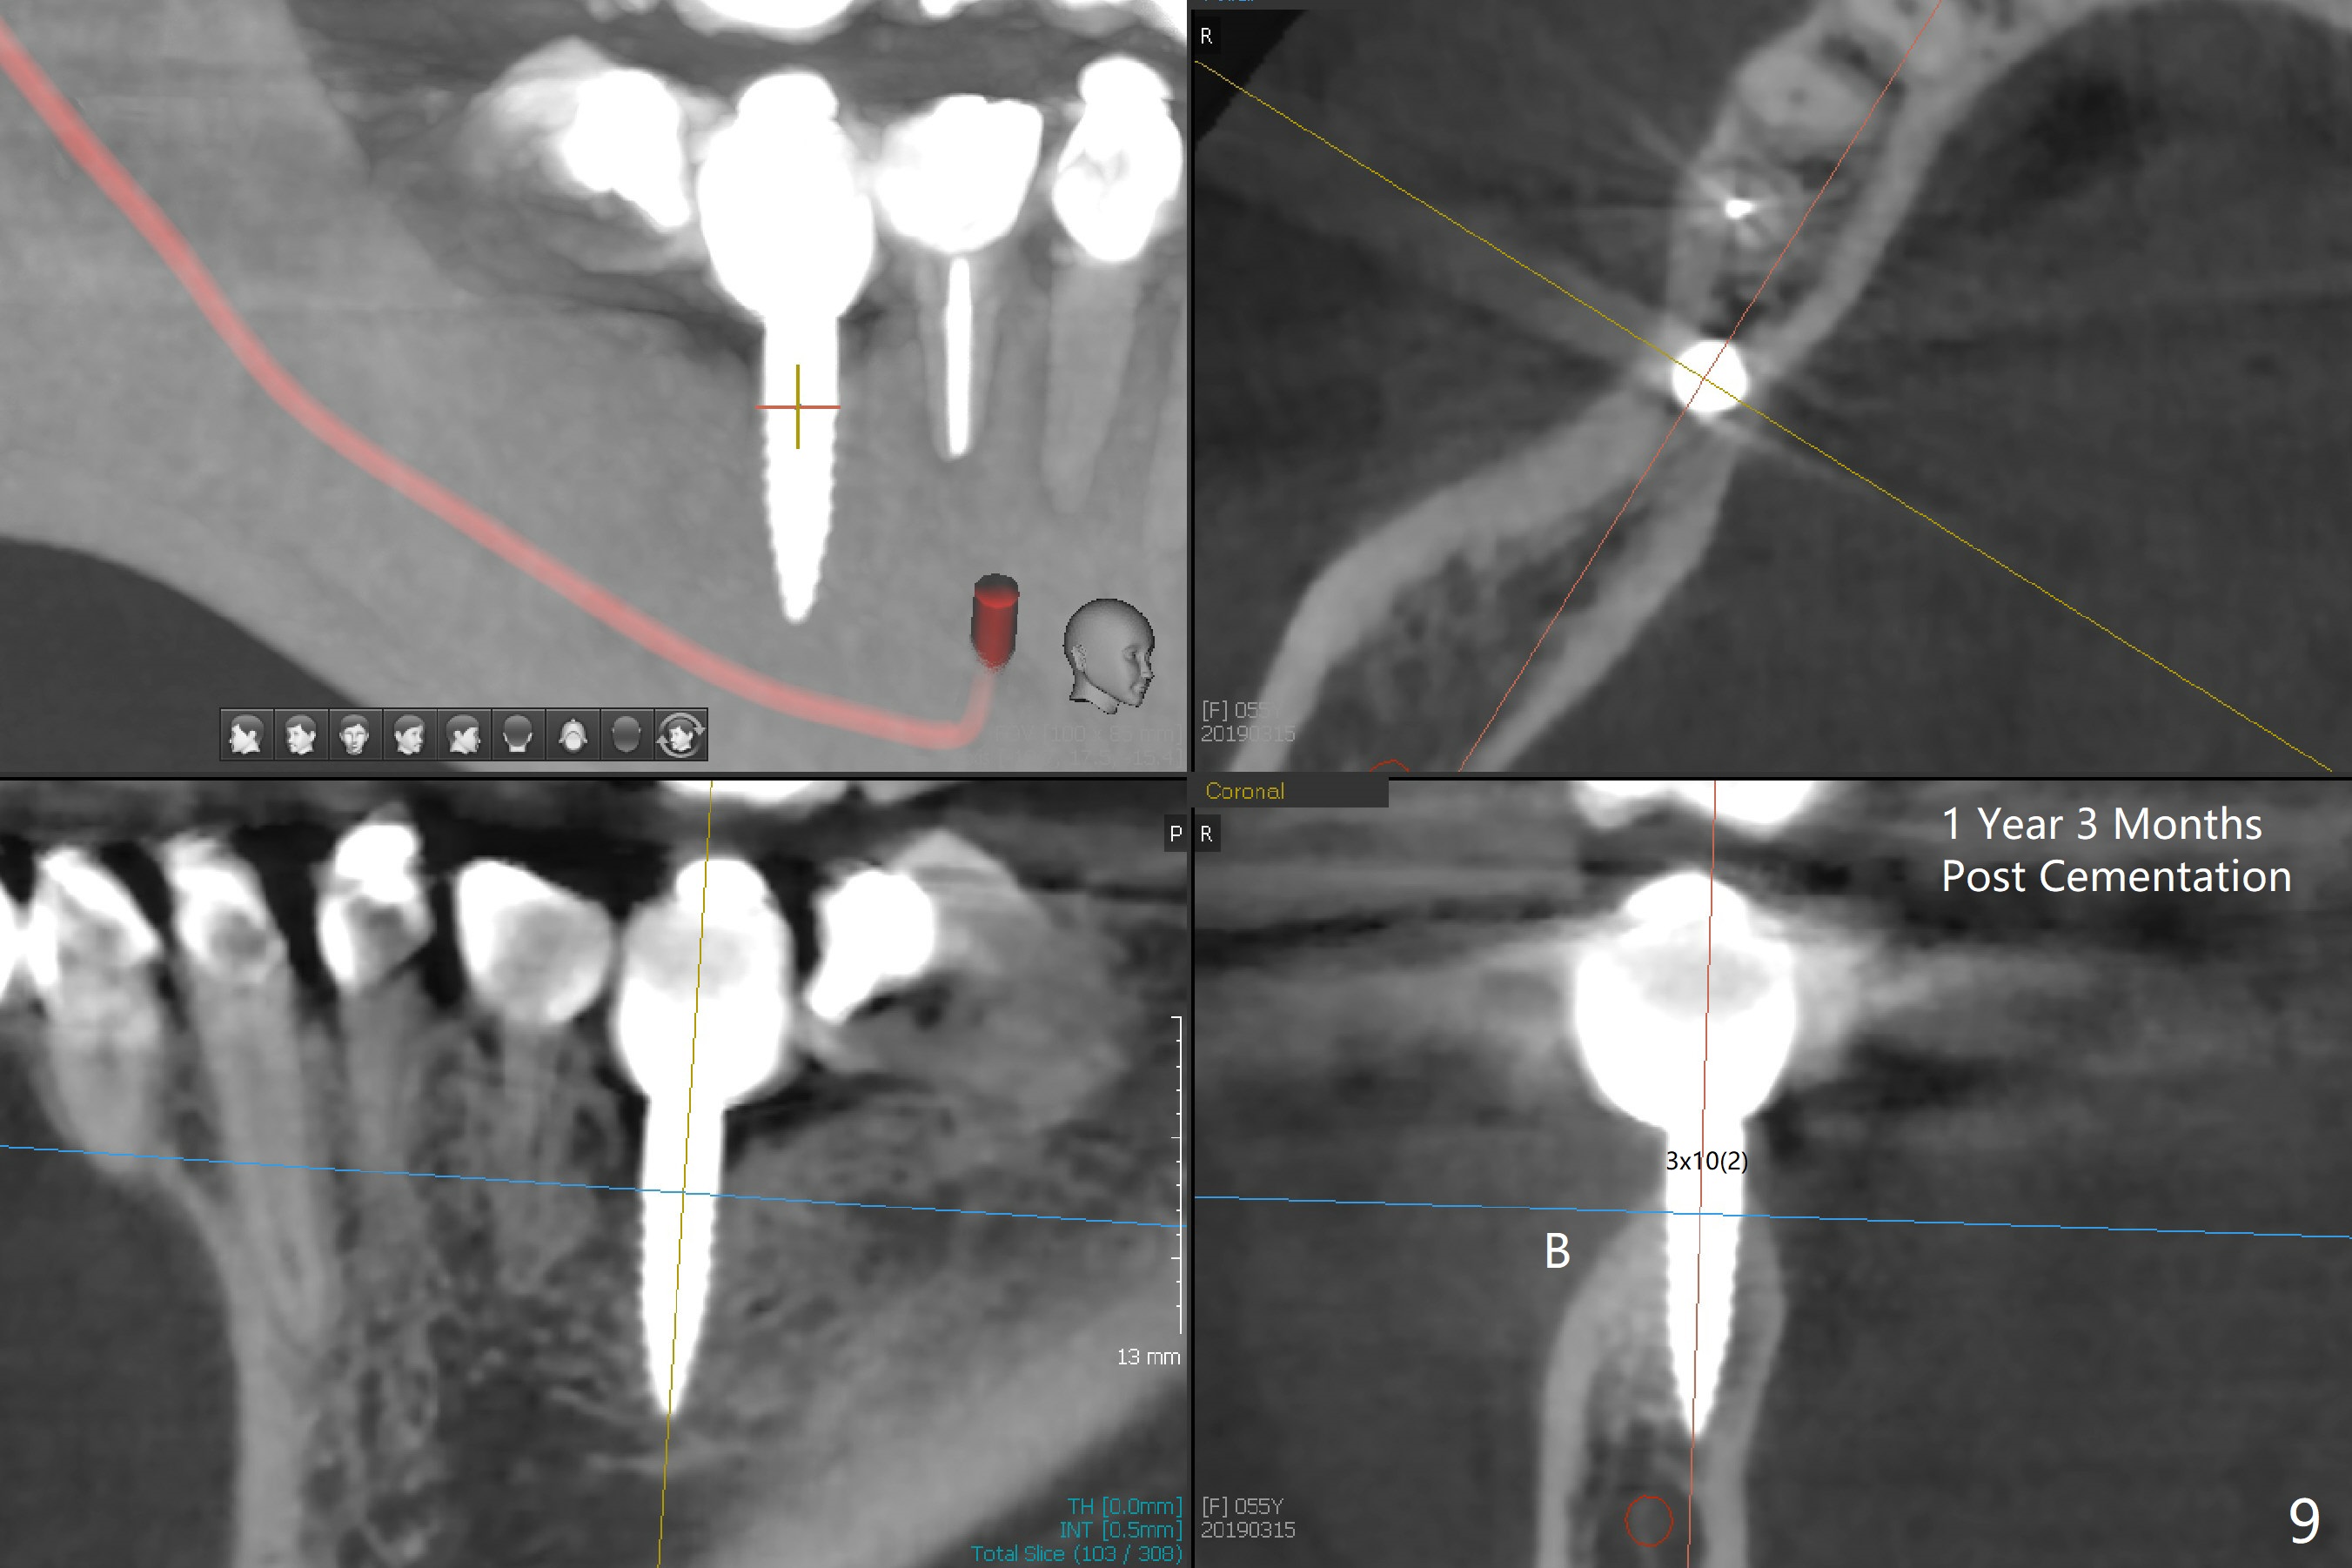

Incision reveals a narrow ridge and a narrow mesiodistal space at #30 (Fig.1). It seems that a 1-piece implant is indicated. Due to limited mouth opening, a 1.2 mm drill is unstable in place after use for 10 mm; instead a 1.5 mm drill is able to be inserted for 8 mm (Fig.2). A 3x10(2) mm 1-piece dummy implant is placed with 40 Ncm at an apparently acceptable level (Fig.3 >). Clinically a few threads are exposed buccally. When a definitive implant with the same dimension is inserted with 45 Ncm, it looks seated too deep (Fig.4,5). The latter is noted after suturing. The implant is backed up for a few turns so that the length of the abutment appears a little more reasonable. Introspectively, a 4 mm cuff should have been used after ridge reduction. Although there is no bone loss 4 months postop (Fig.6), the abutment margin (Fig.7 arrow) is subgingival (red dashed line: gingival margin). Diode laser is used for gingivectomy prior to impression. The bone density around the implant increases 11 months post cementation (Fig.8 *), probably related to recurrent #18 infection. The patient uses floss after meal.